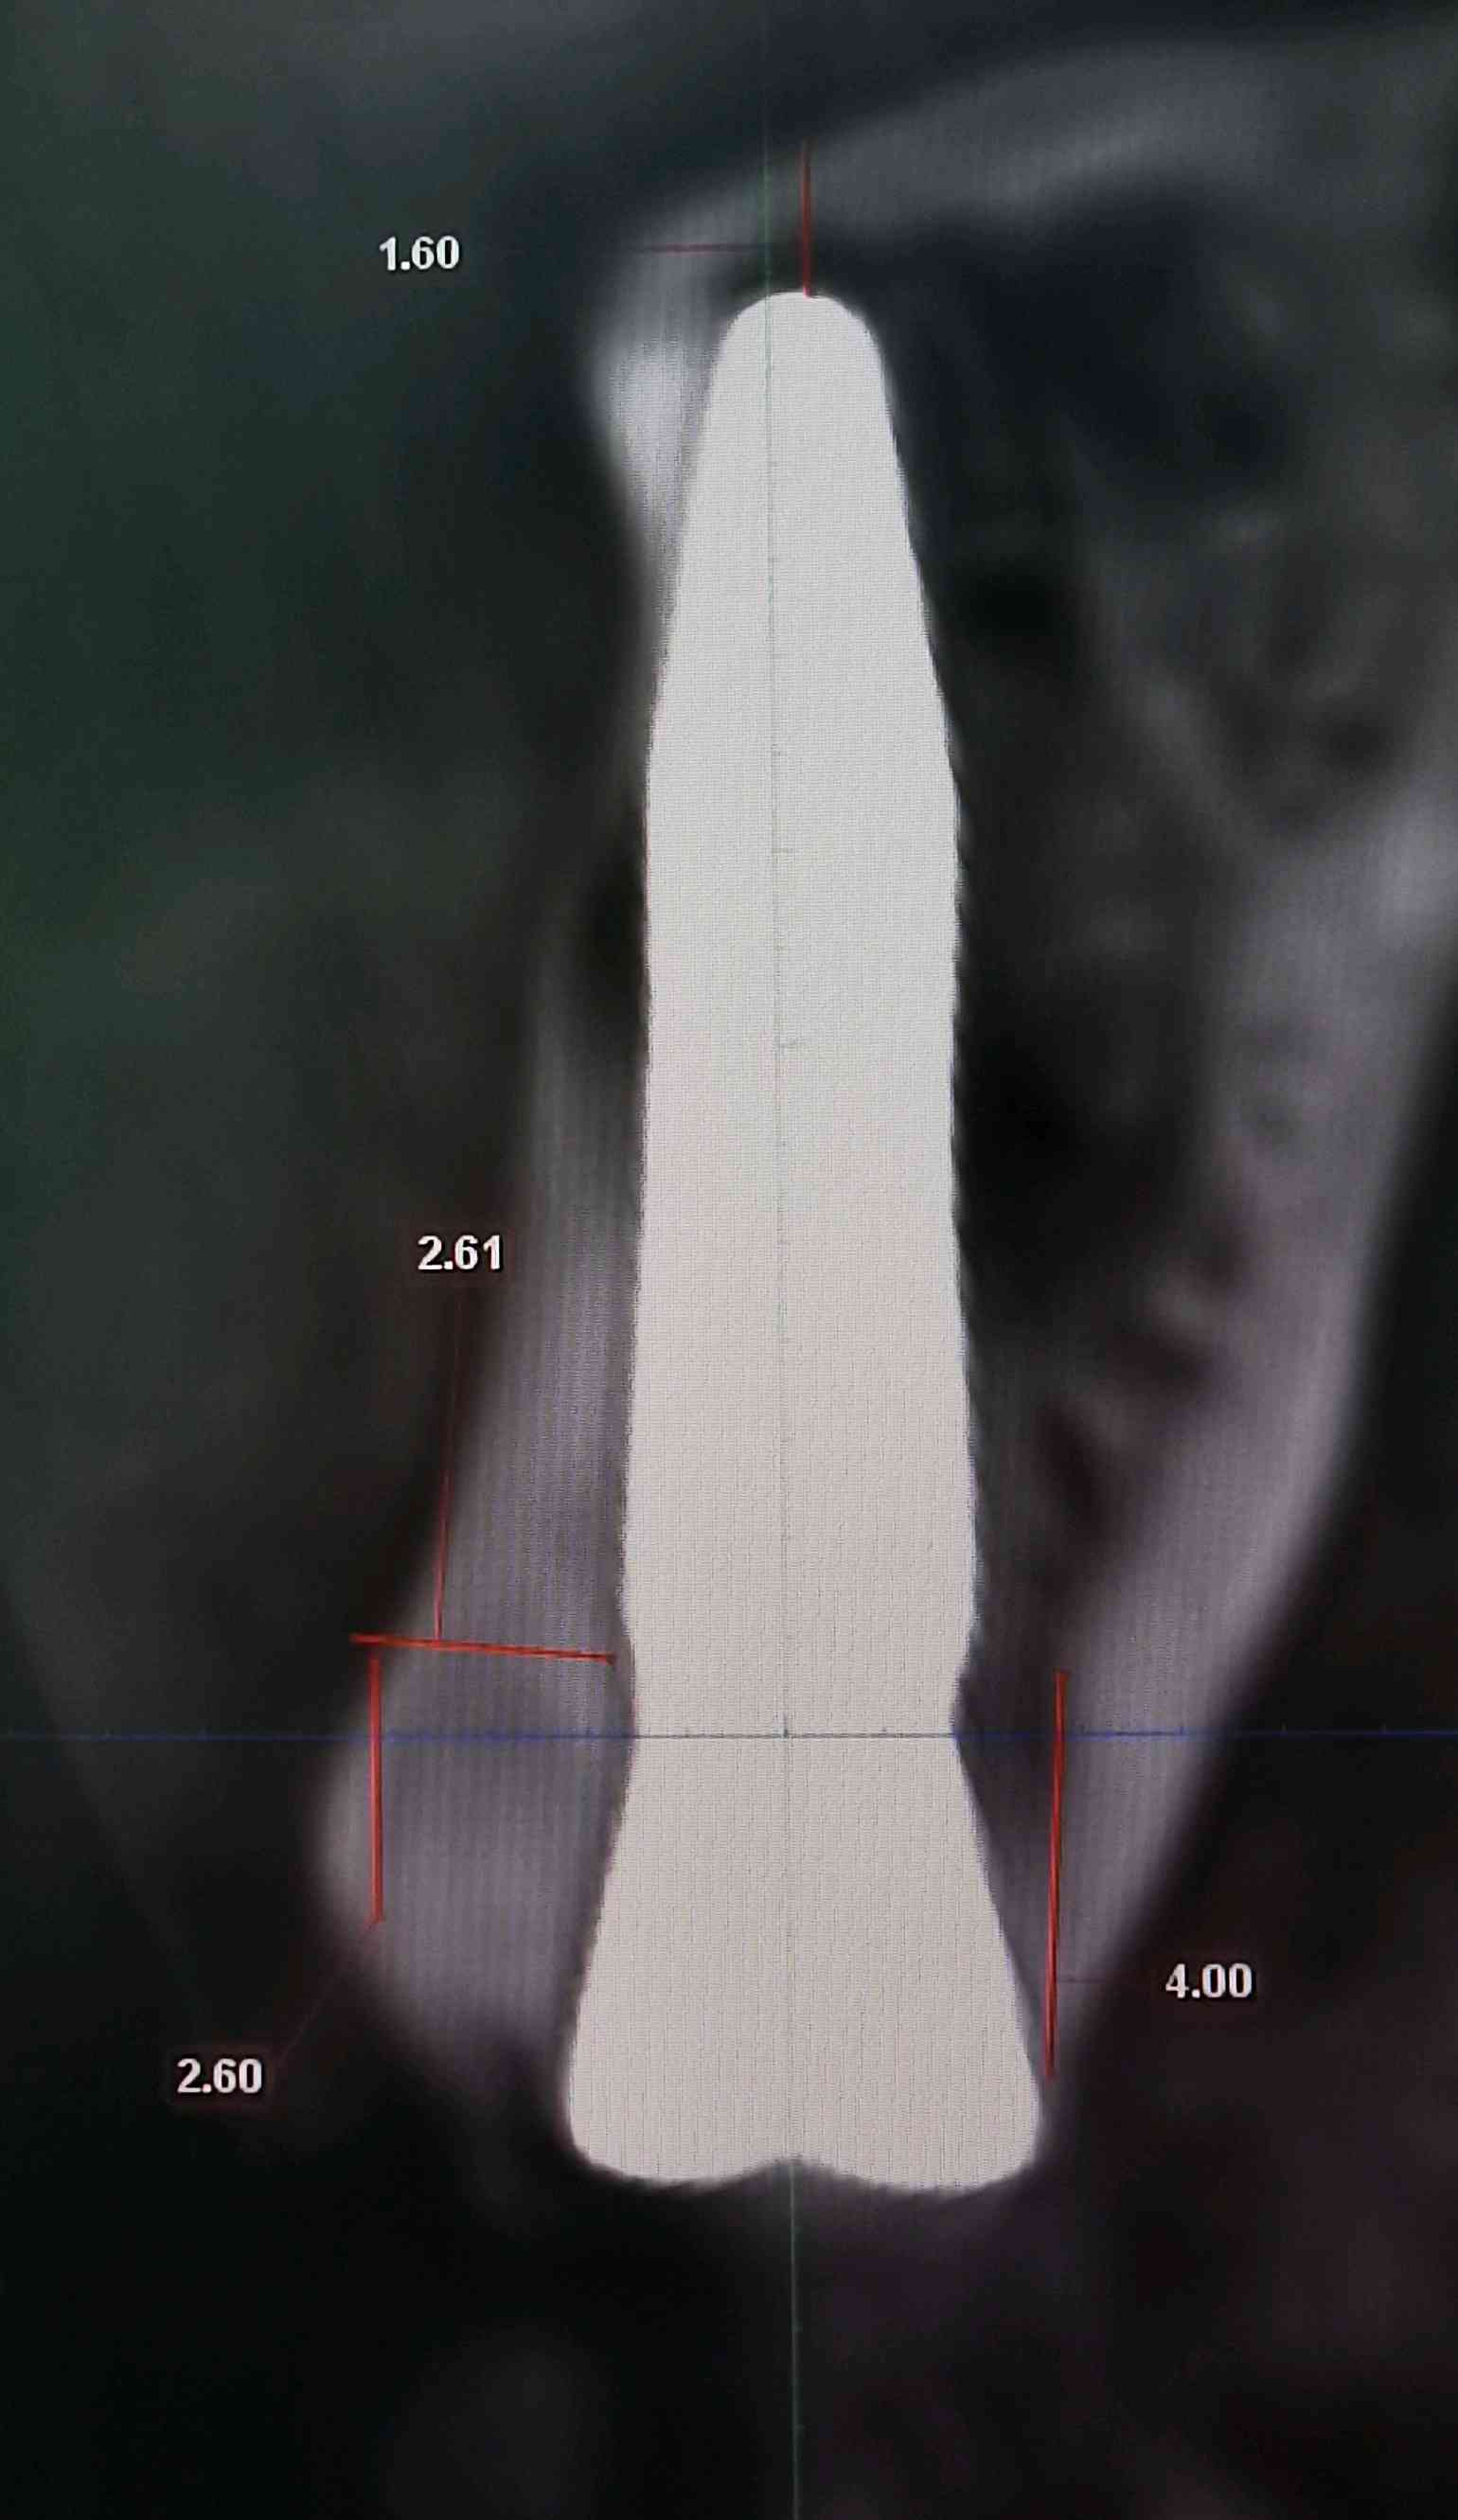

a.术前准备拍摄颌面部 CBCT ,评估骨质骨量,设计种植体植入的位置、轴向、直径和长度。

c、即刻植入根据拔牙窝的位置方向和颌骨的解剖形态,将钻头方向贴着腭侧骨板,采用逐级备洞的方法制备种植窝,植入适当长度和直径的种植体。即刻修复如种植体初期稳定性≥35N/ cm ,可行即刻修复。术中行数字化无痛印模,送工厂行高精度义齿制作,1周内复诊,行义齿戴入,所有即刻修复体均调整至正中、前伸和侧方咬合均无接触。根据种植愈合情况,即刻修复3-6个月后再行永久修复

案例左上2号根尖囊肿

根尖黄豆大小囊肿伴根纵折

3.5倍显微镜下拔牙,刮囊肿,植入ITI 种植体。